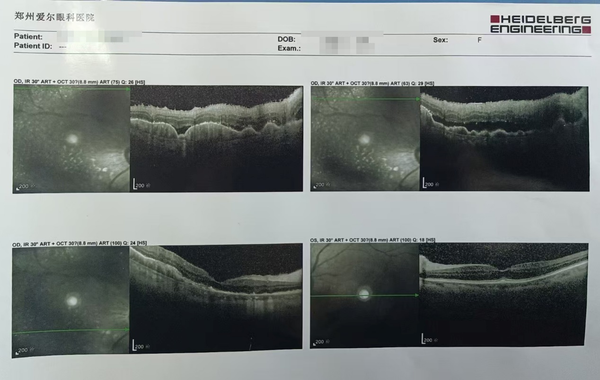

而在OCT(光学相干断层扫描)检查中,赵女士眼底视网膜同样发现了异常,其层间分布了大量中高反射信号,甚至出现了神经上皮和色素上皮的脱离。

▲赵女士OCT检查